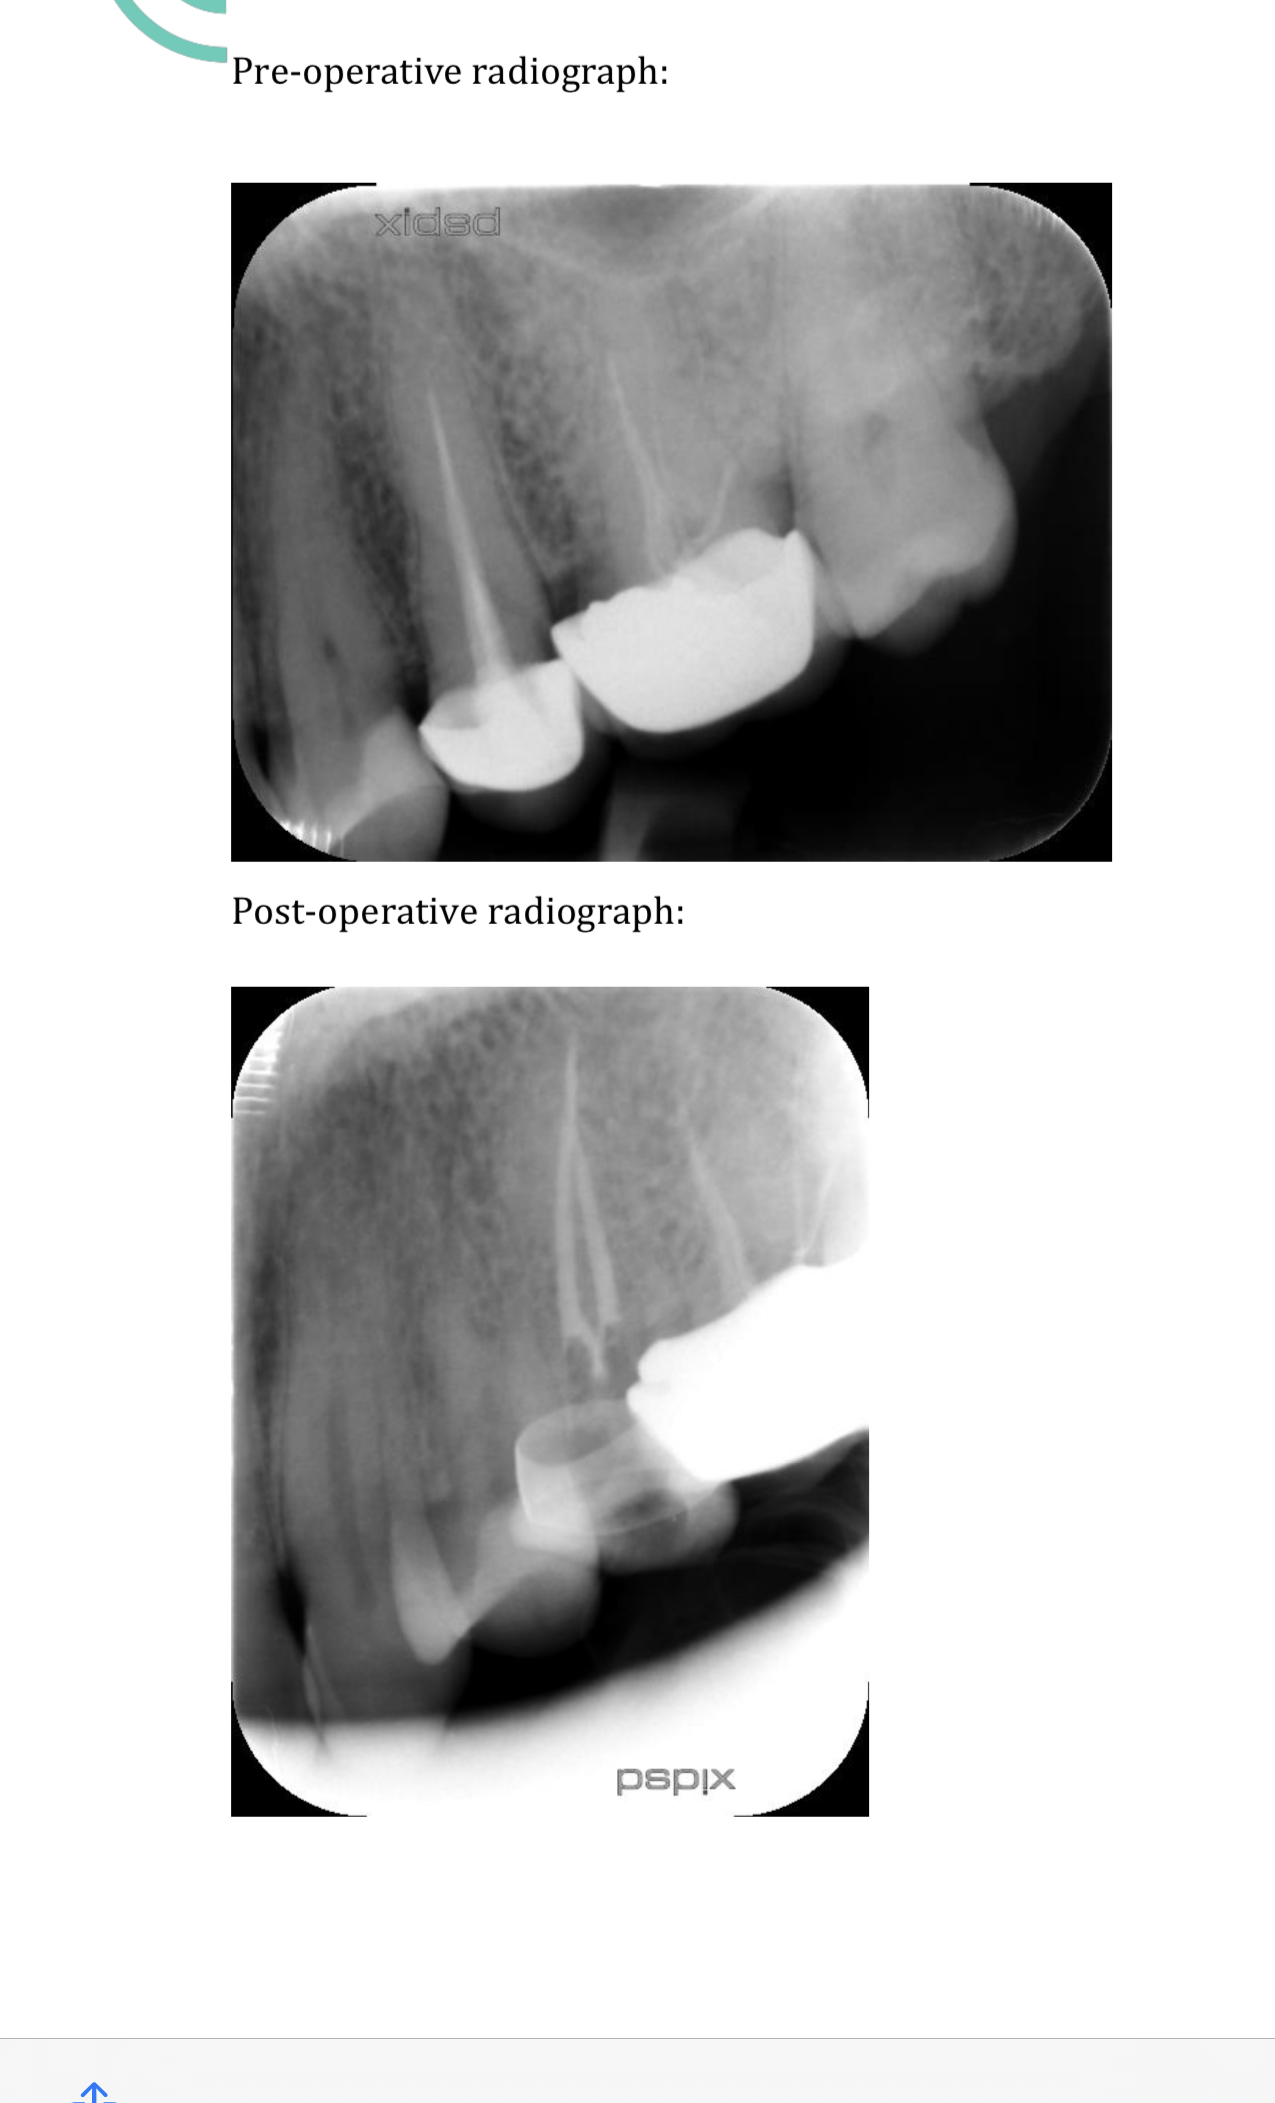

Kindly check the X-ray as I had redone the root canal but still feeling sometimes pain. Dentist said that I ll feel pain for 1-2 months and it’s nearly two months. Is it done properly???

Sorry, the RCT is not done appropriately. You will have to get them done again.

Unfortunately the root canal treatment done in your teeth is not up to the required standard of care. In other words it's been poorly done, which is why you still have pain even after two months.

You will have to have this redone, which means taking the old crown off and doing the root canal procedure all over again, called a re-RCT

Following are the reasons of Ur pain

1) Food impaction in adjacent molar faulty restoration

2) Root canal of Molar is not done properly

3) High spots in filling

4) poor perio or pockets surrounding tooth

root canal not done properly

Nope it's not filled properly

You might need re Do

i will suggest a simple formula for your understanding that is "there would be no pain and senstivity in the tooth or teeth which has gone through the root canal or RCT". remember there if there is pain now would be even after 2 months or might be even 6 months until unless not treated in a true sense.